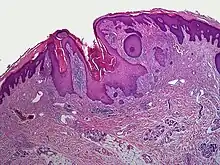

| Dilated pore of Winer |

A dilated pore, also known as a dilated pore of Winer, is a cutaneous condition characterized by a solitary, prominent, open comedo on the face or upper trunk of an individual.[1]: 675 Louis H. Winer is credited with discovering the dilated pore. [2][3]